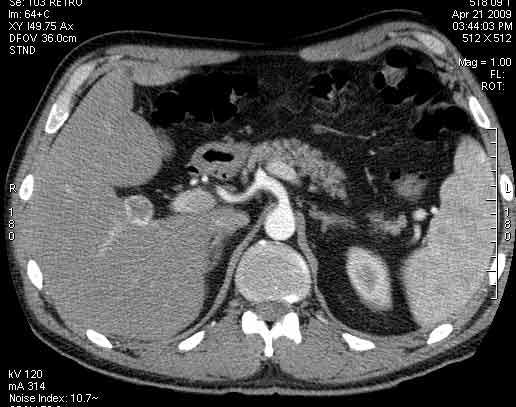

Сонограммы, КТ- артериальная, портальная и отсроченная паренхиматозная фазы

Сделали КТ (весьма похвальная тактика); по КТ: в артериальную фазу: периферическое усиление в виде сливающихся островков контраста, с центрипетальной направленностью. Венозная и отсроченная фаза-хорошее накопление контраста; образование практически изоденсно по отношению к паренхиме печени. Классика гемангиомы. Вуаля-диагноз на "тарелочке".